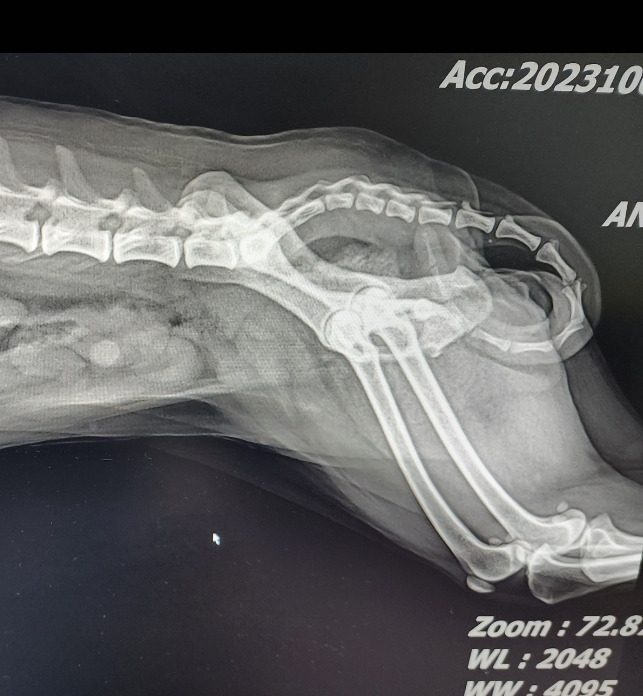

이번엔 CT 영상을 보는 중에 눈에 띄는 장면이 있다.

"쏘피야? 너 많이 무서웠구나? 꼬리를 이렇게 말고 있는 거 보니까? 많이 힘들었구나?"

검사 결과 영상을 쭈욱 둘러보니,

마음이 아프다.

병원에서는 너의 뇌만 보였었는데, 이제와서 보니 다른게 더 많이 보인다.

녀석의 말린 꼬리가 보이고,

녀석이 입에 문 호스가 보인다.

그리고 아무것도 먹지 못해서 비어있는 녀석의 장이 보인다.

쏘피야 네 코야?? 뭐야? 넌 왜 MRI도 귀여워?

꼬리를 저렇게 말고 있는거 보니 많이 무서웠구나? 쏘피야 ㅠㅠ